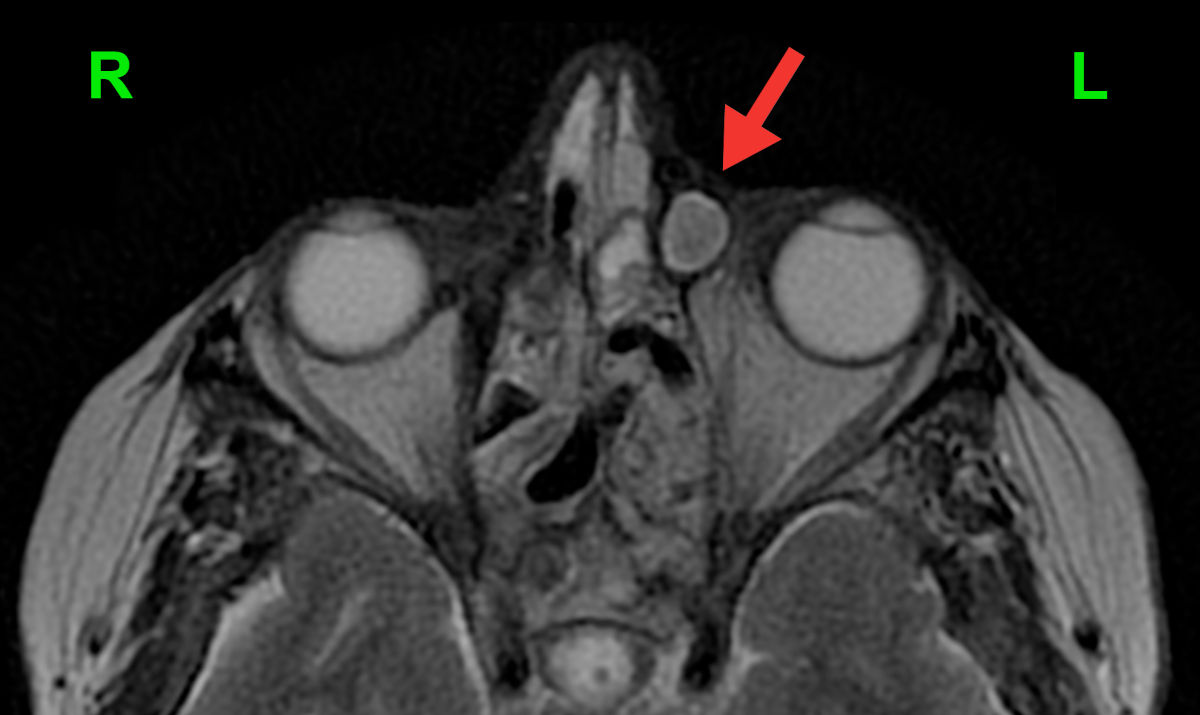

A 73-year-old adult female suffering from granulomatosis with polyangiitis for 10 years, who was receiving immunosuppressive medication of rituximab (MabThera, Roche, Germany), presented with left-sided dacryocele with recurrent acute dacryocystitis episodes (Fig. 1). She had previously undergone a FESS surgery on both sides, and later a laser DCR procedure on the right side, followed by an external DCR on both sides - neither of them successful. However, the right side remained asymptomatic afterwards.

Figure 1. Axial MRI shows a well-defined left-sided dacryocele (enlarged lacrimal sac filled with discharge; red arrow).